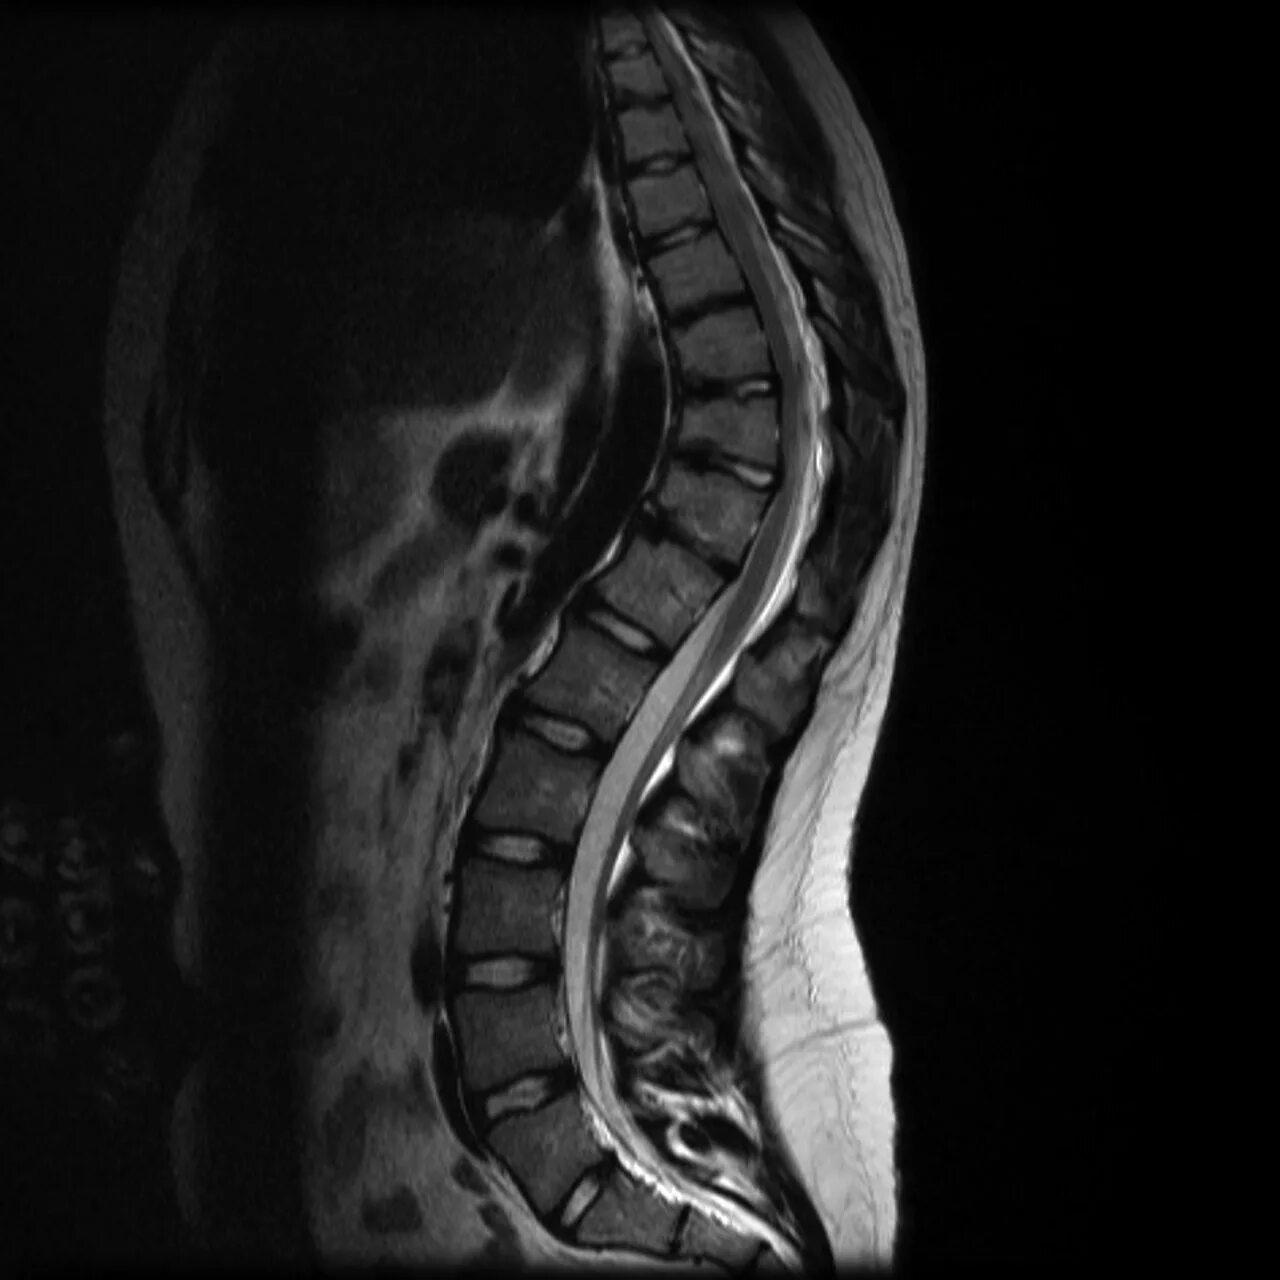

Деформация пояснично крестцового отдела